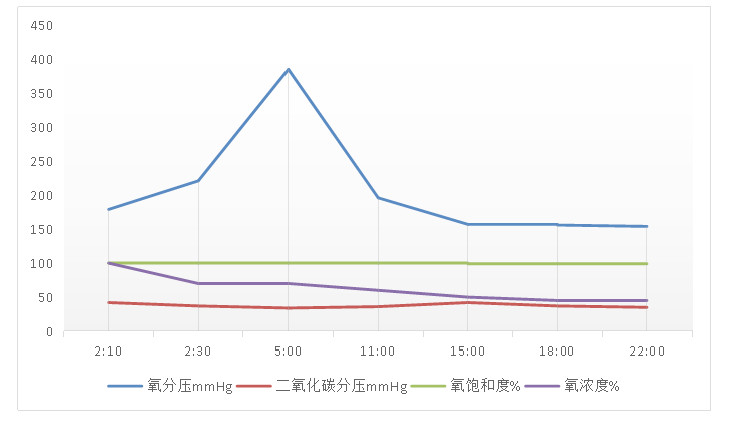

1 临床资料 1.1 病史摘要、体征及辅助检查患者51岁,中年女性,因吸入甲酸甲酯挥发气体后出现“恶心、呕吐,意识改变1h”于2021年6月12日1:30由120急诊送至我院。患者入院后0.5 h迅速出现意识改变,既往体健。入科时查体:体温35℃,脉搏129次/min,呼吸23次/min,血压114/44 mmHg(1 mmHg=0.133 kPa),指脉氧饱和度76%(吸氧状态下、氧流量8 L/min),颜面及四肢皮肤黏膜发绀,衣物上可见少量呕吐物,可闻及刺激性气味。神志恍惚,双侧瞳孔圆形等大、光反射敏感。对答基本切题。双肺呼吸音粗,可闻及少量湿性啰音。入院时胸部X片示:双肺斑片状渗出影(见图 1)。入院后约0.5 h出现意识丧失,立即行经口气管插管接呼吸机辅助呼吸同时建立中心静脉输液通道。辅助检查:白细胞13.11×109/L;中性粒细胞比率95.30%;降钙素原0.02 ng/mL;血生化:肌红蛋白 < 21.00 ng/mL、脑利钠肽前体497.6 pg/mL、丙氨酸氨基转移酶11.0U/L、天门冬氨酸氨基转移酶13.8 U/L、肌酐45 μmol/L、血钾3.37 mmol/L。心肌酶未见异常。动脉血气分析:pH 7.35,PO2 179 mmHg,PCO2 42 mmHg,lac 3.3 mmol/L,SPO2 100%(FiO2 100%)。中心静脉血气分析:pH 7.34,PO2 21 mmHg,PCO2 45 mmHg,ScvO2 31%,lac 2.9 mmol/L(FiO2 100%),经计算氧合指数小于200 mmHg,见图 2及附图1。

| 图 2 患者入院24 h动脉血血气分析趋势图 |

2 讨论ARDS各种肺内或肺外原因导致的以顽固性低氧血症为临床特征的综合征,其临床表现多急性起病、呼吸困难及难以纠正的低氧血症。ARDS还可使肺淋巴回流减少及腺体分泌增多等[3]。根据2012年“ARDS柏林定义”,结合该患者临床表现、体征且在吸氧浓度为100%下,计算氧合指数(PaO2/FiO2)≤200 mmHg,结合胸部X线表现,排除心源性肺水肿后,明确诊断为ARDS(中度)[4-5],故根据急性呼吸窘迫综合征保护性通气策略[6-7]进行辅助通气治疗。根据患者入住ICU时动脉血气分析及中心静脉血气分析动态趋势图所提示,患者发病初期(02:30~05:00时间段)动脉血氧分压(PO2)及中心静脉血氧饱和度(ScvO2)呈正相关表现,而相同时间段内中心静脉动脉血二氧化碳分压差值(Pcv-aCO2)未见增大,说明患者虽存在休克,但在众多导致中心静脉血氧饱和度降低的原因中,组织灌注不足对其影响不明显,而导致中心静脉血氧饱和度降低的主要原因为肺部通换气障碍引起氧供的减少[8]。